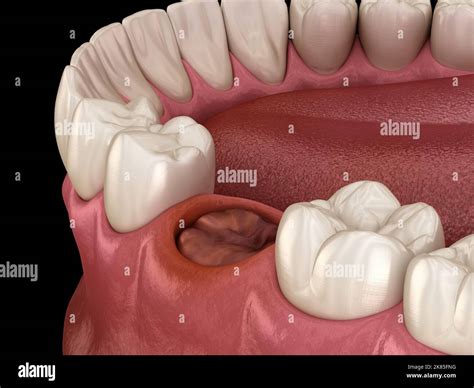

Undergoing a dental extraction is a common procedure, yet the period immediately following the surgery is critical for your recovery. The most vital component of this healing process is the formation and preservation of an after extraction blood clot. This clot acts as a natural bandage over the empty socket, protecting the underlying bone and nerve endings while facilitating the growth of new tissue. If this clot is dislodged or dissolves prematurely, you risk developing a painful condition known as dry socket. Understanding how to protect this clot is essential for a smooth, pain-free recovery.

Following the removal of a tooth, your body immediately triggers a clotting response to stop bleeding. This gelatinous mass is the foundation of your recovery. Without it, the jawbone remains exposed to the oral environment, leading to intense pain that can radiate to your ear, eye, or temple. Protecting the after extraction blood clot is not just about comfort; it is about preventing infection and ensuring the healing progresses at the intended pace.

The clot typically remains in place for 7 to 10 days while the gum tissue begins to close over the site. During this timeframe, the clot undergoes a maturation process, turning from a deep red to a whitish or yellowish color, which is a normal part of the healing cycle. It is important to distinguish between normal healing processes and the actual loss of the clot.